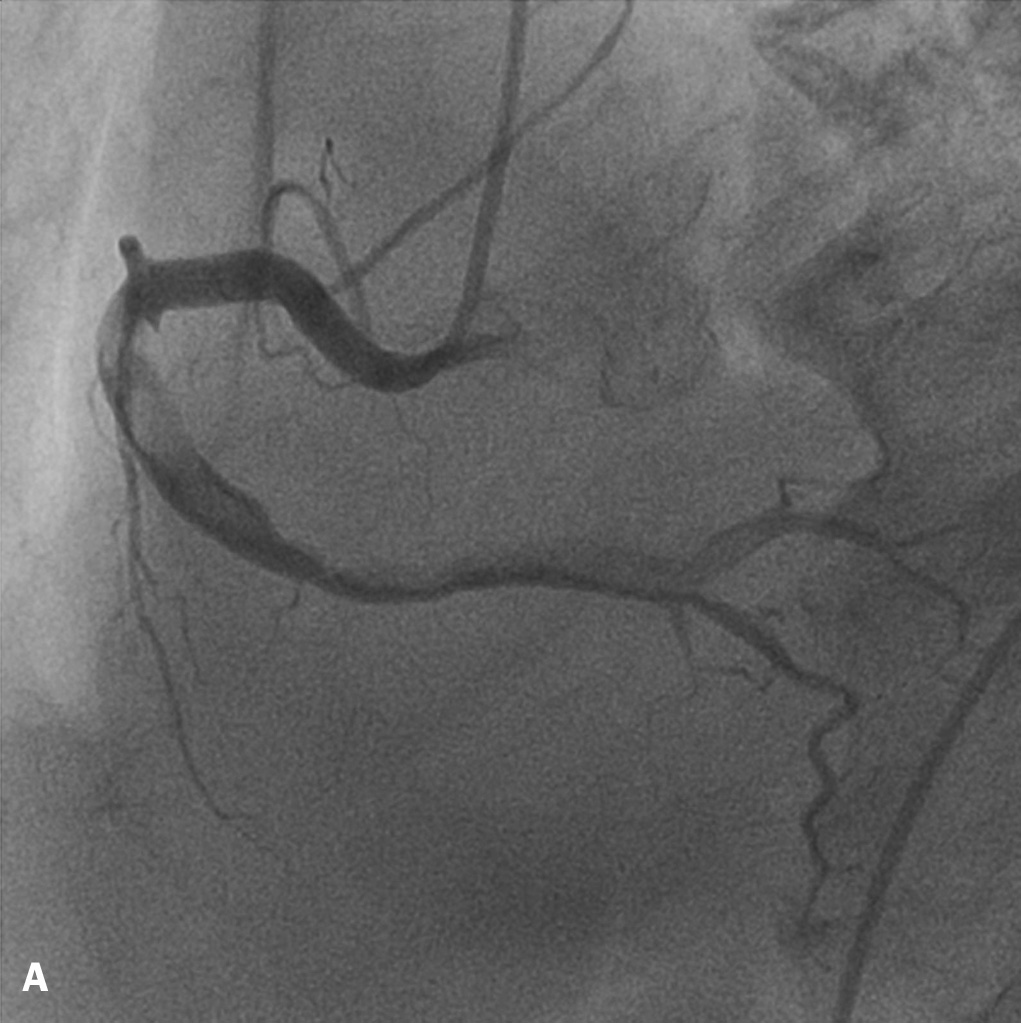

A 65-year-old man presented with a non-ST-elevation acute coronary syndrome. His medical history was unremarkable. Apart from a brother, who sustained a myocardial infarction at the age of 40, no cardiovascular risk factors were present. Coronary angiography revealed normal left anterior descending and circumflex arteries. The right coronary artery was subtotally occluded with an extensive thrombus running into the posterolateral branch (figures 1A and B). Despite appropriate medical treatment, intermittent chest pain persisted. The patient underwent a percutaneous coronary intervention with mechanical removal of the thrombus by aspiration followed by balloon dilatation. During the 12 hours preceding this procedure a glycoprotein IIb/IIIa receptor antagonist was continuously infused, while aspirin, clopidogrel, and a low-molecular-weight heparin (LMWH) were also administered. The intervention was only partially successful with limited restoration of right coronary perfusion resulting in a TIMII flow. Following the procedure, intermittent chest pain persisted initially but subsided after a few days of continued administration of aspirin, clopidogrel and an LMWH.